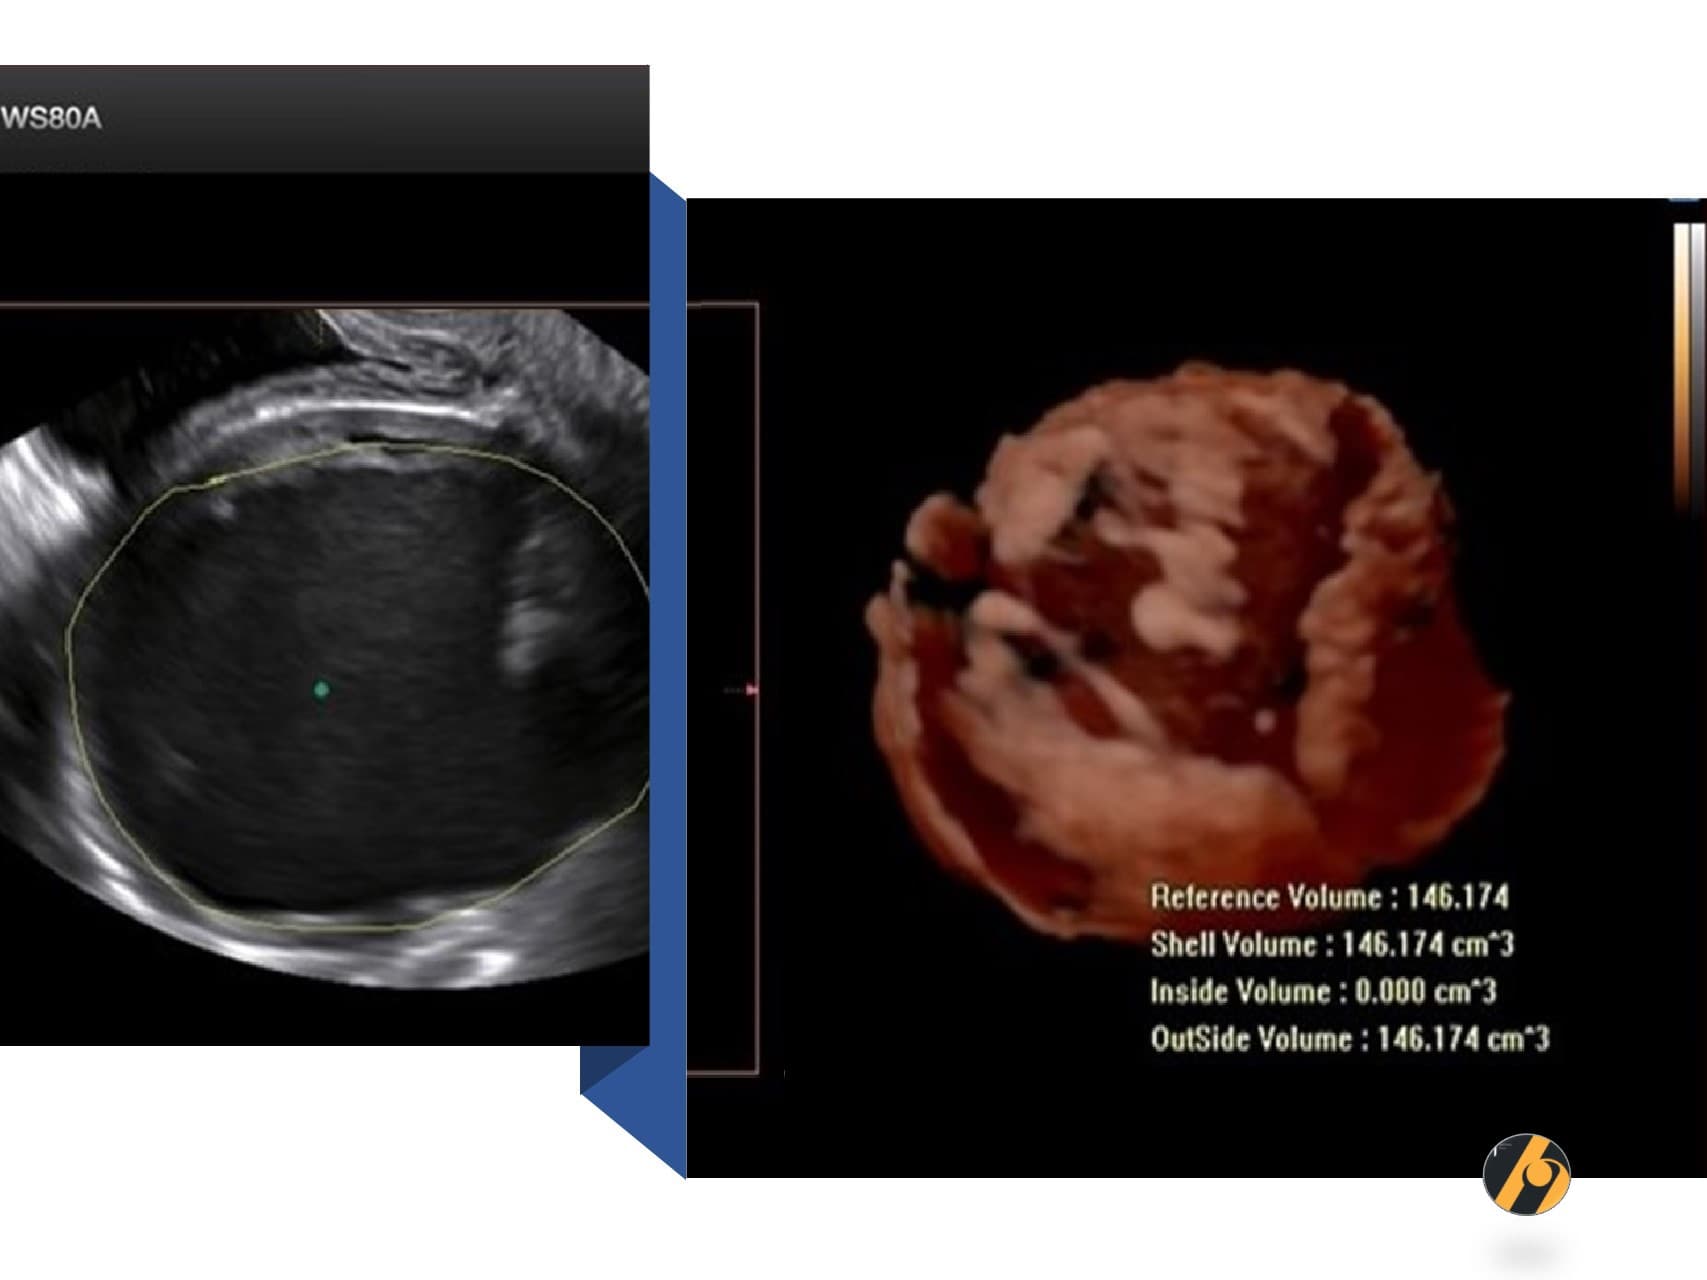

Premda su laparoskopija i patohistološka dijagnostika zlatni standard u dijagnostici endometrioze, u postavljanju dijagnoze od pomoći mogu biti i drugi manje invazivni postupci. Nažalost, ove tehnike kao što su transvaginalna sonografija i magnetska rezonancija nisu u stanju otkriti manje ili lezije koje su manje aktivne. Transvaginalna ultrazvučna dijagnostika učinkovito otkriva endometriotička žarišta čiji je promjer veći od 19 mm (¾ incha).